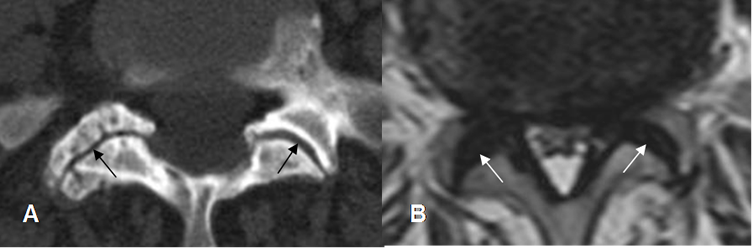

Fig 67. Articulaciones intervertebrales.

A: TAC axial. Hipertrofia de articulaciones interfacetarias, con fenómeno del vacío en el lado derecho.

Fig 68. Articulaciones intervertebrales.

A: TAC axial y B: RM axial en T2. Hipertrofia de articulaciones intervertebrales, con disminución de los espacios interfacetarios.